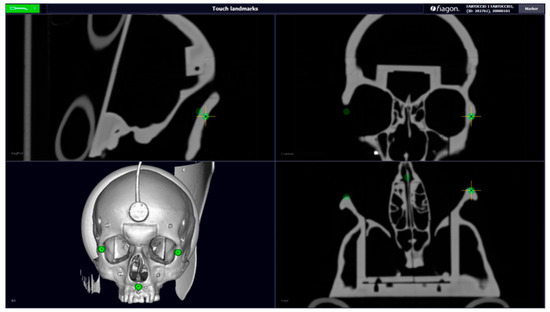

For each calibration, we evaluated the error of each sphere, between the position of the pointer and the position of the sphere in the CT, and calculated the measurements of each distance. After calibration, we used the command “Length”; it is present in the Fiagon Navigation Software (Version 3.7) module and allows you to measure the distance in millimeters. We used the spheres placed in different anatomical areas (Figure 8) to verify the accuracy of both sensors, the one placed on the front and the one placed on the created support.

2.6. Fiagon Measures

For each calibration performed, we calculated seven distances and the location error of each sphere. We calculated the length in millimeters between each sphere with the integrated software of the neuronavigator (Fiagon Navigation Software Version 3.7). The electromagnetic navigator allowed us to take screenshots of each measurement performed (Figure 9 and Figure 10).

Figure 9. Example: measure distance.

Figure 10. Error localization sphere nr.5.